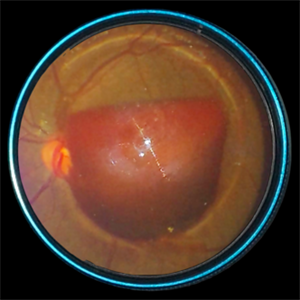

SUBHYALOID HEMORRHAGE

Jul 27 2022 by Prithvi Chandrakanth

A 54-year-old male presented with sudden diminution of vision with visual acuity of 3/60 in the Left eye. visual acuity of the Right eye was 6/6, fundus examination revealed subhyaloid hemorrhage in the Left eye and normal fundus in the Right eye.

Photographer: Dr.Prithvi Chandrakanth, Department of Vitreoretinal Services, Aravind Eye Hospital, Coimbatore

Imaging device: TRASH TO TREASURE RETCAM - SMARTPHONE FUNDUS CAMERA

Condition/keywords: SHH, subhyaloid hemorrhage